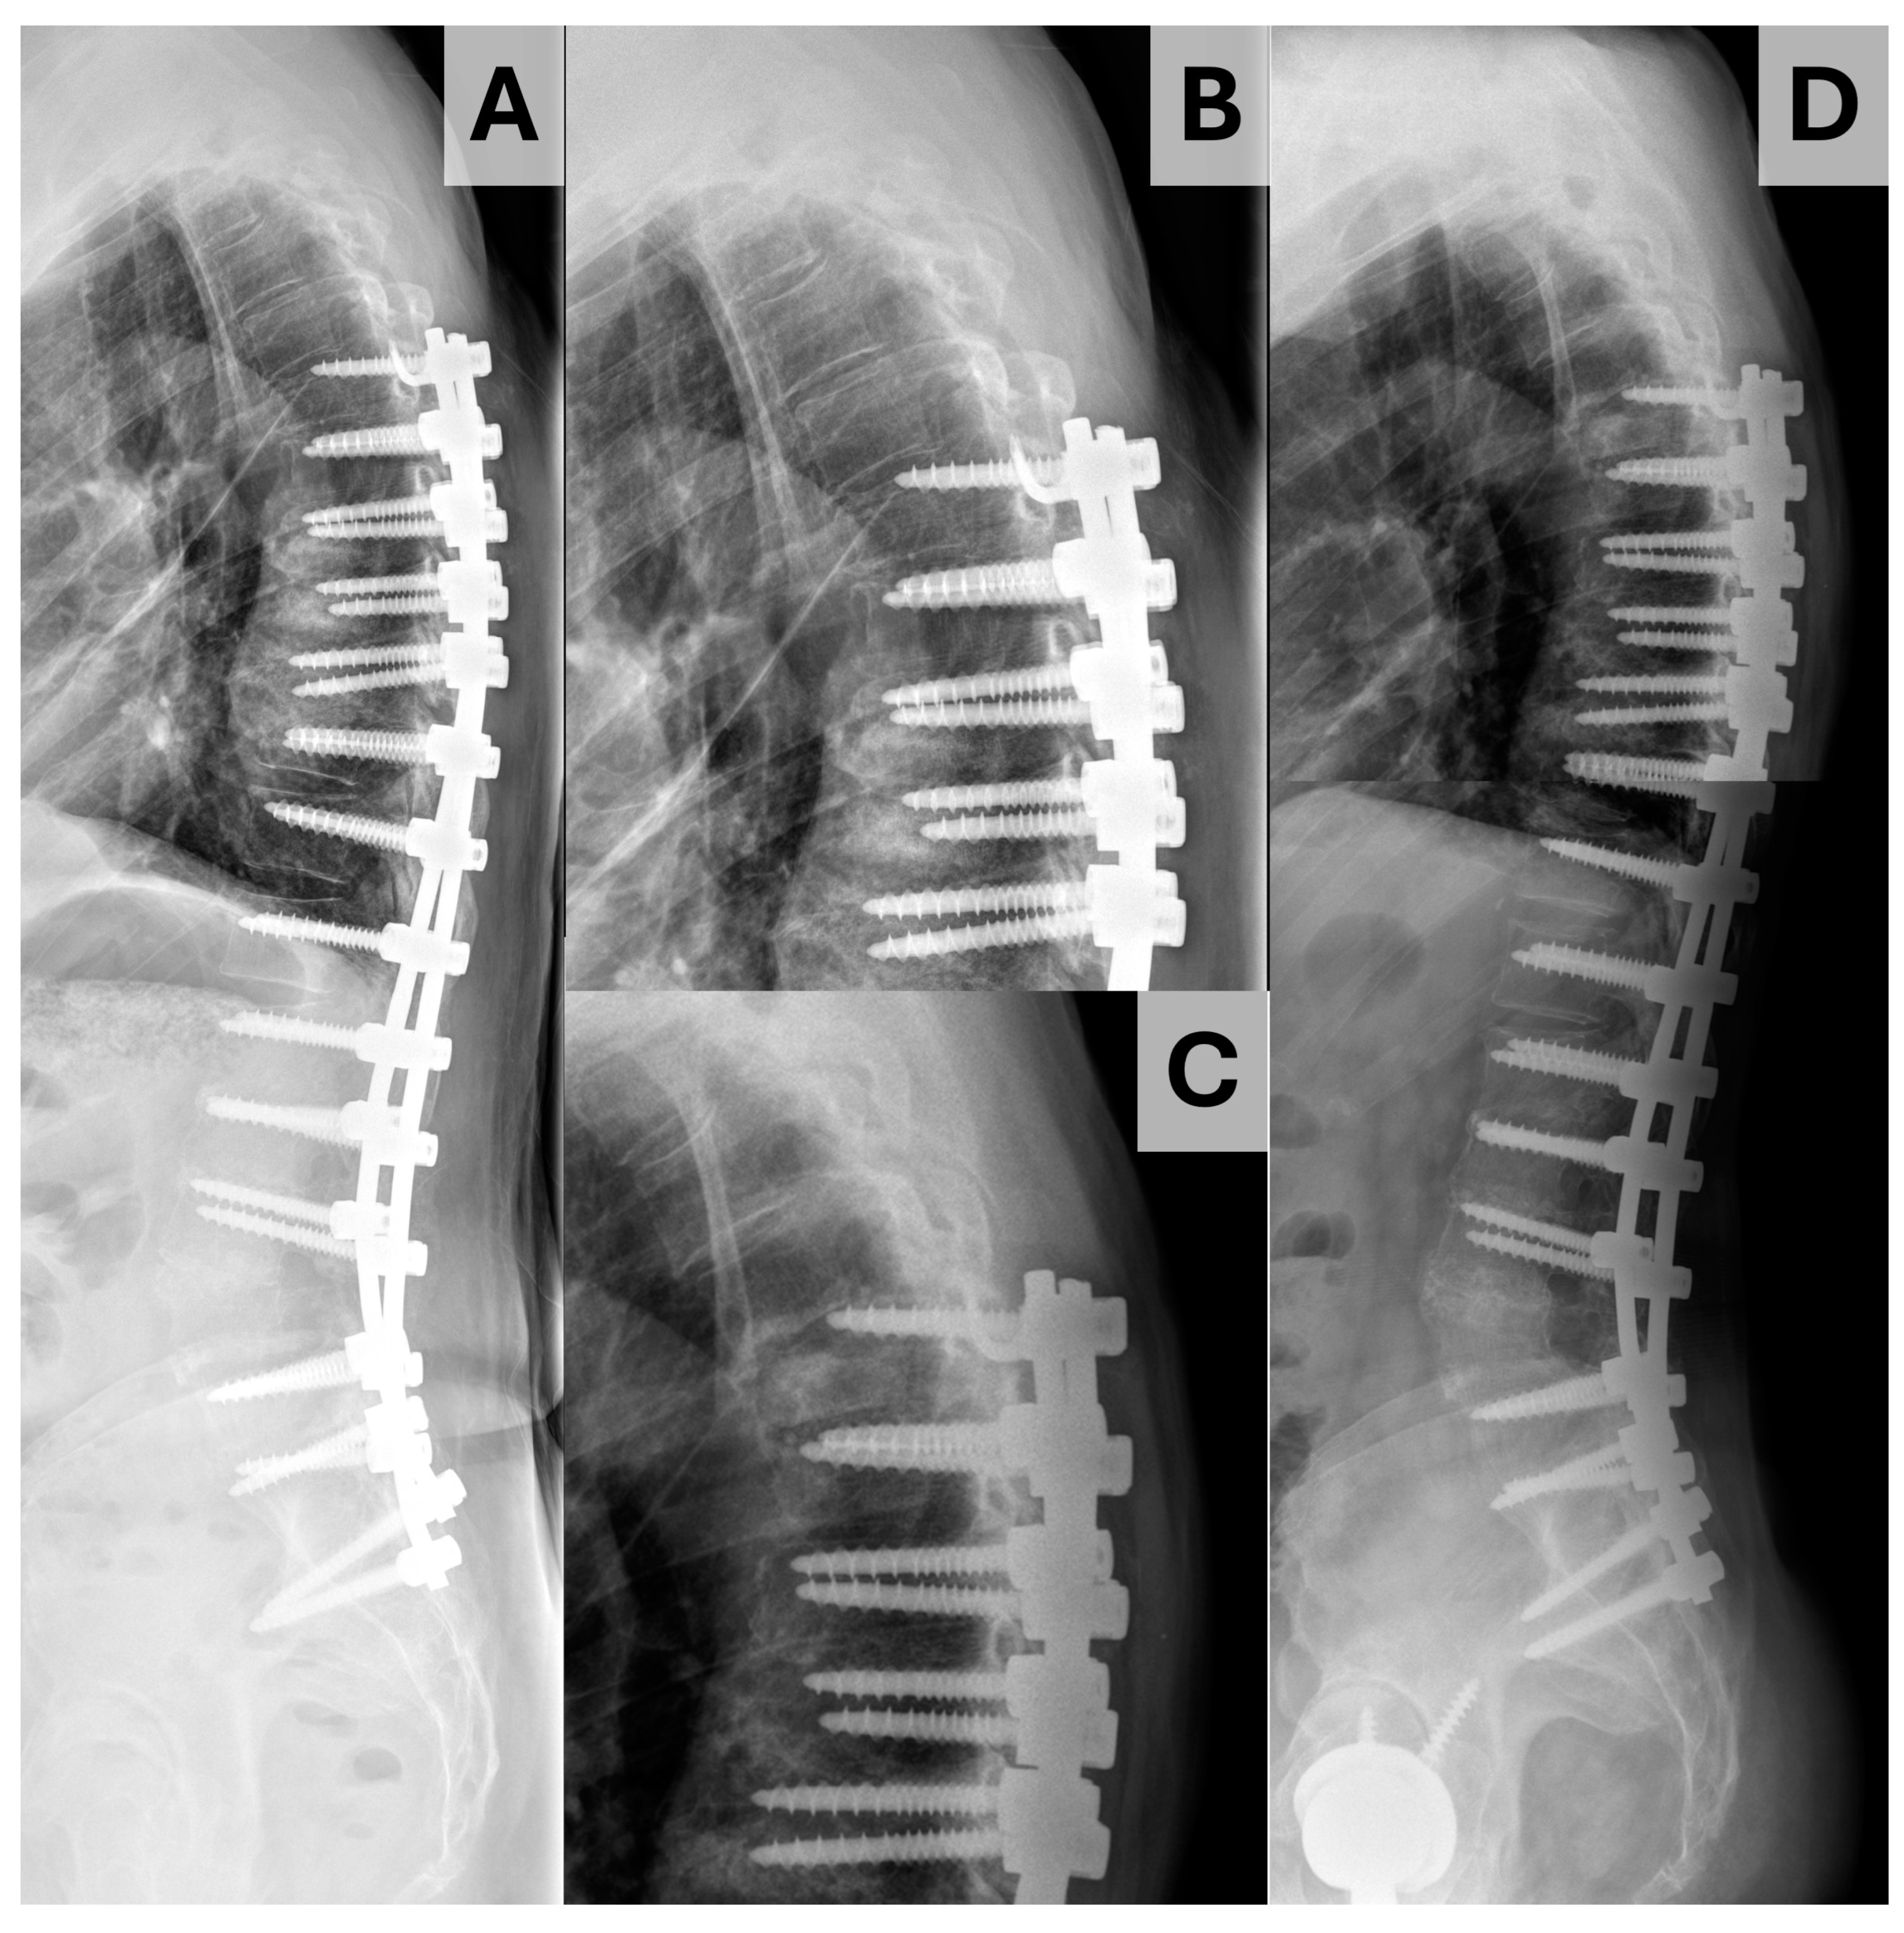

2. Materials and Methods